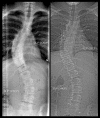

Figure 1

The left image shows a traditional whole spine radiograph. The right image shows the scout picture obtained with low-dose CT in the same patient. The images were taken on the same day before planned corrective surgery.